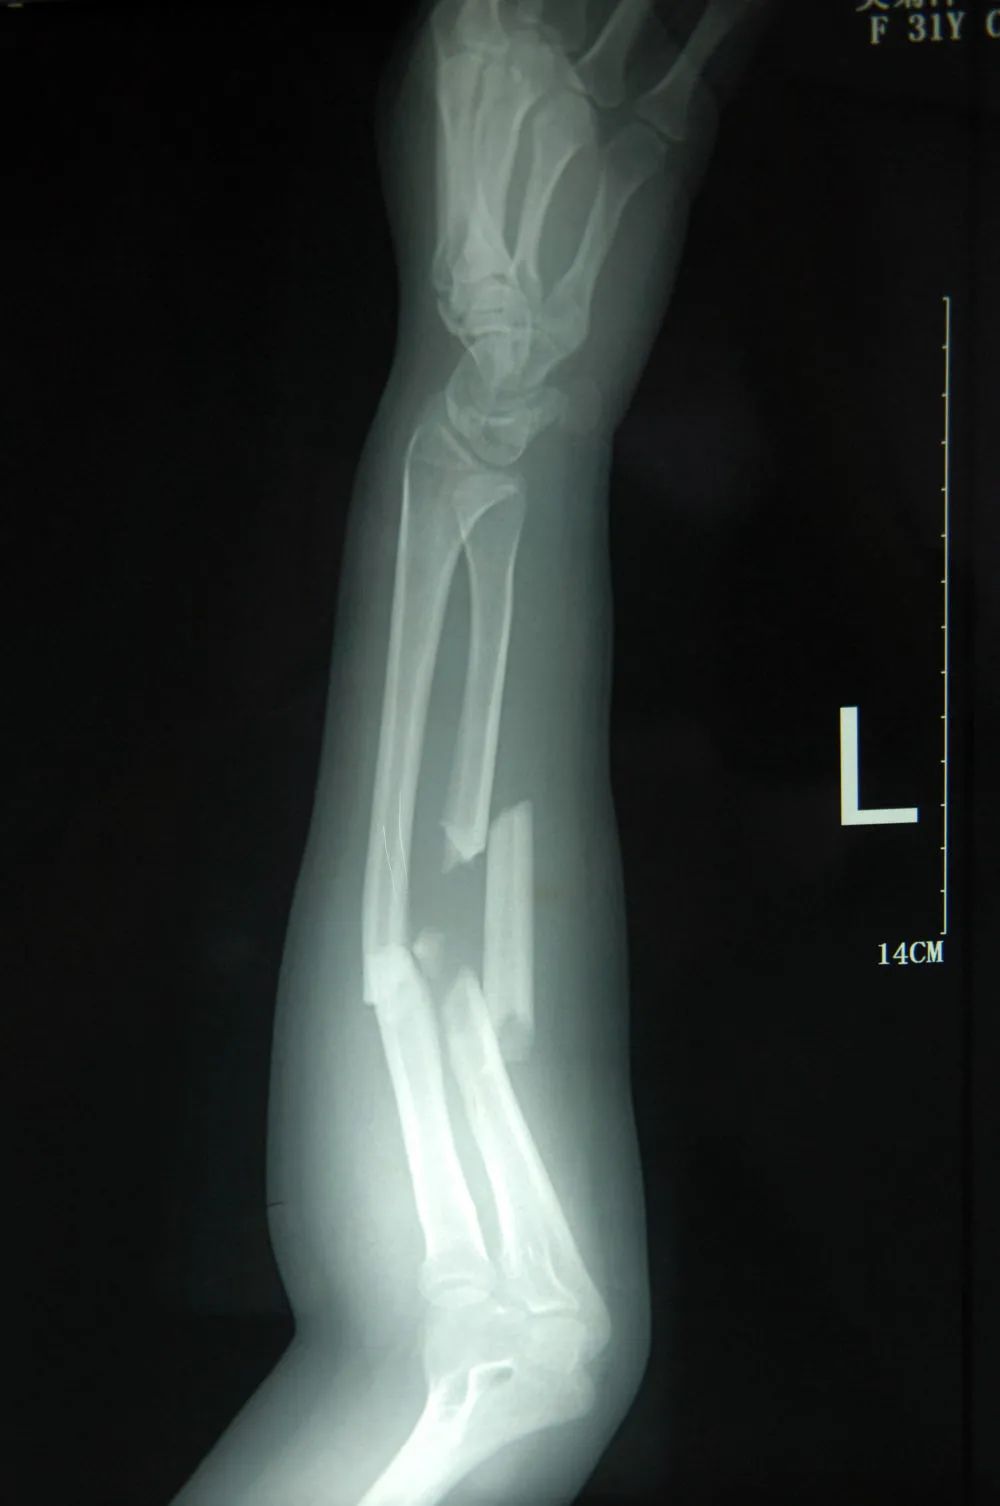

X光片显示:吴菊萍左手臂的尺桡骨断成了三截,伤势非常严重,需要立即手术!

尺桡骨是人手臂中最精巧的一根骨头,不仅起支撑作用,还负责手臂旋转功能。

金登峰副院长是著名的骨伤科专家,他表示曾见过大大小小的尺桡骨骨折,但像吴女士这样严重的,以前只在车祸伤中看到过。

吴菊萍的左臂尺桡骨断成三截